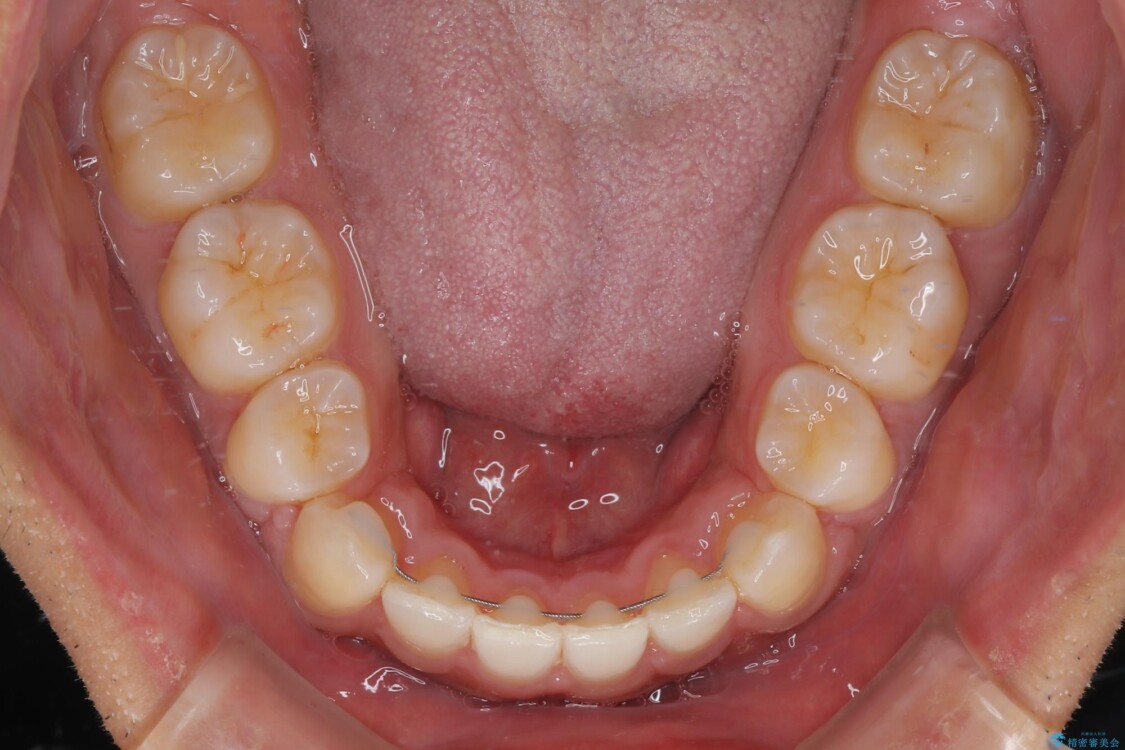

治療後

• 八重歯と前歯のガタガタを抜歯矯正で治療|クリアブラケット使用例 治療後画像

八重歯はきれいに整い、前歯もバランスよく収まり、横顔のラインも自然に改善されました。

治療後、患者様は「思い切り笑えるようになった」と大変喜んでくださいました。